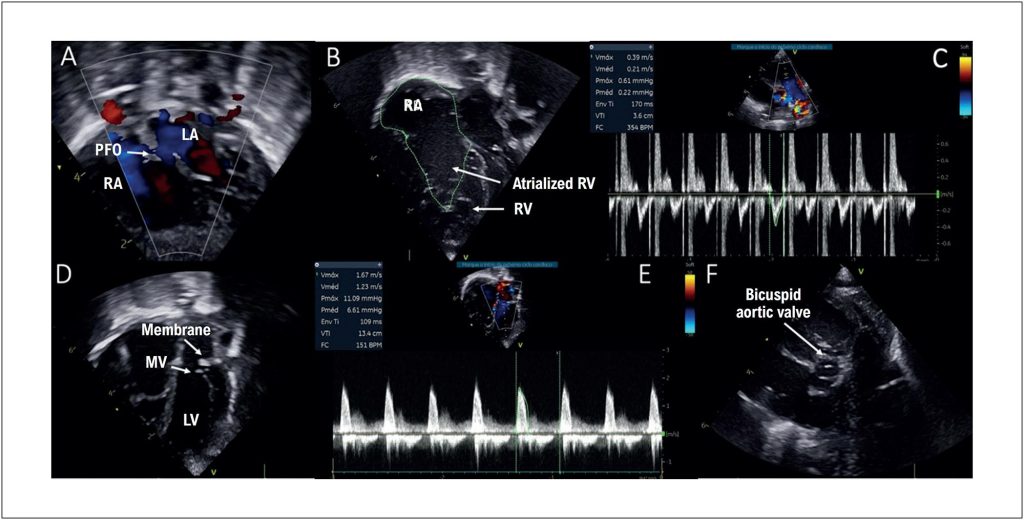

Ebstein’s anomaly is a complex congenital heart disease that occurs in one out of every 200,000 live births. Its association with left-sided obstructive lesions is rare and poses significant challenges for both clinical and surgical management. In this case report, we present a newborn patient with Ebstein’s anomaly associated with supravalvular mitral stenosis and coarctation of the aorta (CoA), who underwent cardiac catheterization for the implantation of a post-dilatable stent in the aortic isthmus via the carotid approach.